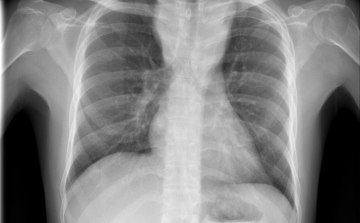

Már a 26. tüdőátültetést végezték el Magyarországon

A 26. tüdőátültetést végezték el Magyarországon a közelmúltban - közölte az Országos Onkológiai Intézet és a Semmelweis Egyetem hétfőn az MTI-vel.

Elvégezték az első magyar tüdő- és vesetranszplantációt egy műtét keretében

Elvégezték az első magyarországi tüdő- és vesetranszplantációt egy műtét keretében június 30-án - tudatta az Országos Onkológiai Intézet hétfőn az MTI-vel.

Elhagyhatta a kórházat az első magyarországi tüdőátültetésen átesett férfi

Jó általános állapotban elhagyhatta az Országos Onkológiai Intézetet (OOI) az a férfi, akin először hajtottak végre tüdőtranszplantációt Magyarországon.

Először hajtottak végre tüdőtranszplantációt Magyarországon

Először hajtottak végre tüdőtranszplantációt Magyarországon, a műtét sikeres volt - jelentették be az operációt végző szakemberek és az Országos Onkológiai Intézet vezetője szombaton Budapesten.